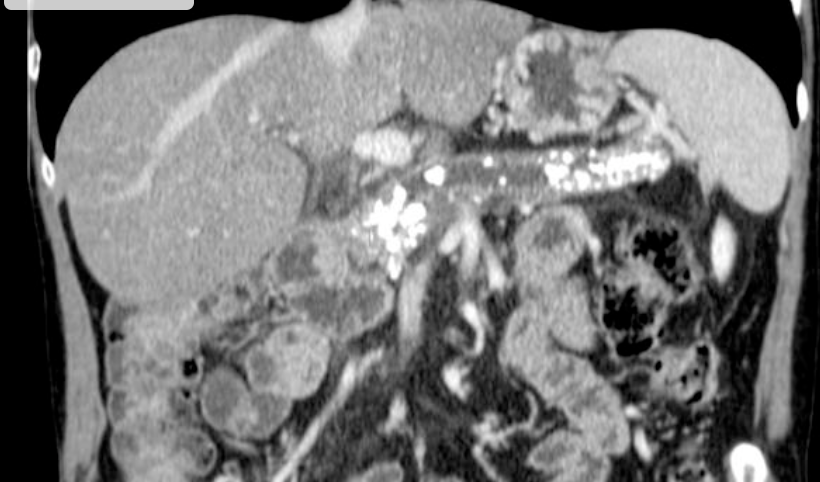

Radiology Findings of Autoimmune Pancreatitis

Single phase CT scan (multiphase scans not performed due to age of patient) demonstrates a diffusely enlarged pancreas with a “halo” like rim of hypoattenuating tissue which is smoothly marginated. Minimal peripancreatic fat stranding.

Associated splenic vein thrombosis, splenomegaly and cavernous transformation of the portal vein.